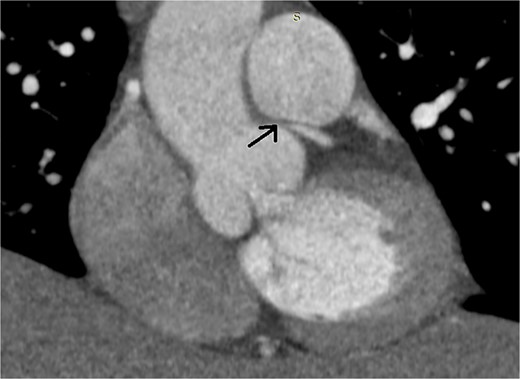

A 46-year-old female presented with recurrent chest pain radiating to the left arm accompanied by dyspnea. She was a non-smoker with no significant past medical history. Physical examination, laboratory results, chest X-ray, and electrocardiogram were all normal. Transthoracic echocardiography showed normal valvular function, a left ventricular ejection fraction of 63%, and mildly impaired diastolic function. Multislice computed tomographic coronary angiography revealed sub-total occlusion of the left main coronary artery, starting at the ostium and extending 5 mm distally (Fig. 1). Cardiac catheterization revealed a right-dominant coronary circulation, with a 90% stenosis in the ostial and proximal shaft of the left main coronary artery, with no other lesions detected (Fig. 2).

Preoperative multislice computed tomographic coronary angiography revealing sub-total occlusion of left main coronary artery, starting at the ostium and extending 5 mm distally (arrow)